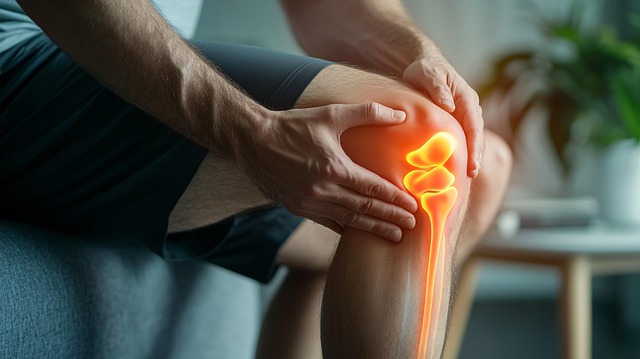

무릎통증 원인, 단순한 통증이 아닌 구조적 문제

무릎 통증의 대표적인 원인은 다음과 같다.

- 퇴행성 관절염: 연골이 닳아 관절 간 마찰이 증가하면서 통증 유발. 50대 이후 여성에게 흔하다.

- 반월상 연골 손상: 스포츠나 외부 충격으로 발생하며, 무릎이 ‘잠기는 느낌’과 함께 통증이 나타난다.

- 십자인대 파열: 격한 운동 중 무릎이 꺾이거나 돌아가면서 발생. 부기와 관절 불안정성이 동반된다.

- 비만: 무릎에 지속적인 체중 압력이 가해져 통증 유발

- 자세 불균형: 양반다리, 쪼그려 앉기, 무릎 꿇는 자세 등은 연골 마모를 가속화한다.

- 체온 저하 및 혈액순환 문제: 겨울철 유독 심한 무릎 통증은 혈류 문제에서 기인하기도 한다.